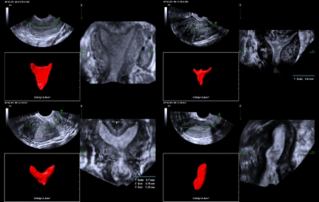

![ultrasonic-diagnosis-mullerian-duct-anomalies.thumb.319.319 Ultrasound Journal 39 - Ultrasonic Diagnosis of M├╝llerian Duct Anomalies]() Ultrasound Journal 39 - Ultrasonic Diagnosis of M├╝llerian Duct AnomaliesHow 3D transvaginal ultrasound replaced MRI for detecting uterine malformations. Septate uterus case demonstrates Smart ERA's role in reproductive imaging. Evidence-based diagnosis.Ultrasound Cases | Ultrasound | Smart applications | OB GYN 2025-12-04

Ultrasound Journal 39 - Ultrasonic Diagnosis of M├╝llerian Duct AnomaliesHow 3D transvaginal ultrasound replaced MRI for detecting uterine malformations. Septate uterus case demonstrates Smart ERA's role in reproductive imaging. Evidence-based diagnosis.Ultrasound Cases | Ultrasound | Smart applications | OB GYN 2025-12-04 -

![smart-era-diagnosis-mullerian-duct-abnormalities.thumb.319.319 Ultrasound Journal 33 - Use of Smart ERA in diagnosis of Ultrasound Journal 33 - Use of Smart ERA in diagnosis of M├╝llerian duct abnormalities duct anomalies]() Ultrasound Journal 33 - Use of Smart ERA in diagnosis of Ultrasound Journal 33 - Use of Smart ERA in diagnosis of M├╝llerian duct abnormalities duct anomaliesDiscover how Mindray's Smart ERA technology revolutionizes the diagnosis of M├╝llerian duct abnormalities using AI-based 3D ultrasound, providing accurate and automated endometrial cavity imaging for improved gynecological care.Ultrasound Cases | Intelli-Digital | Ultrasound | OB GYN 2025-01-14

Ultrasound Journal 33 - Use of Smart ERA in diagnosis of Ultrasound Journal 33 - Use of Smart ERA in diagnosis of M├╝llerian duct abnormalities duct anomaliesDiscover how Mindray's Smart ERA technology revolutionizes the diagnosis of M├╝llerian duct abnormalities using AI-based 3D ultrasound, providing accurate and automated endometrial cavity imaging for improved gynecological care.Ultrasound Cases | Intelli-Digital | Ultrasound | OB GYN 2025-01-14